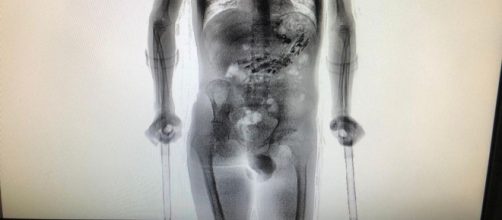

Após retornar de uma saída temporária de sete dias, o detento, que sofre de uma deficiência física, foi flagrado com 62 objetos dentro do estômago. A constatação dos objetos foi realizada por meio de um aparelho scanner.

A fim de fazerem uma vistoria mais detalhada no corpo do detento, os policiais o encaminharam para o Complexo Penitenciário do Estado, localizado na cidade de São Pedro de Alcântara, onde foi realizada uma nova inspeção de imagens com um aparelho mais moderno capaz de scanear o corpo humano e gerar imagens mais detalhadas.

Ao passar pelo scanner, foi possível detectar a presença de diversos objetos metálicos no estômago do detento.

Ao todo, foram encontrados dez aparelhos celulares e mais outros 52 objetos metálicos, tais como cabos USB, isqueiro, e uma quantidade de drogas.